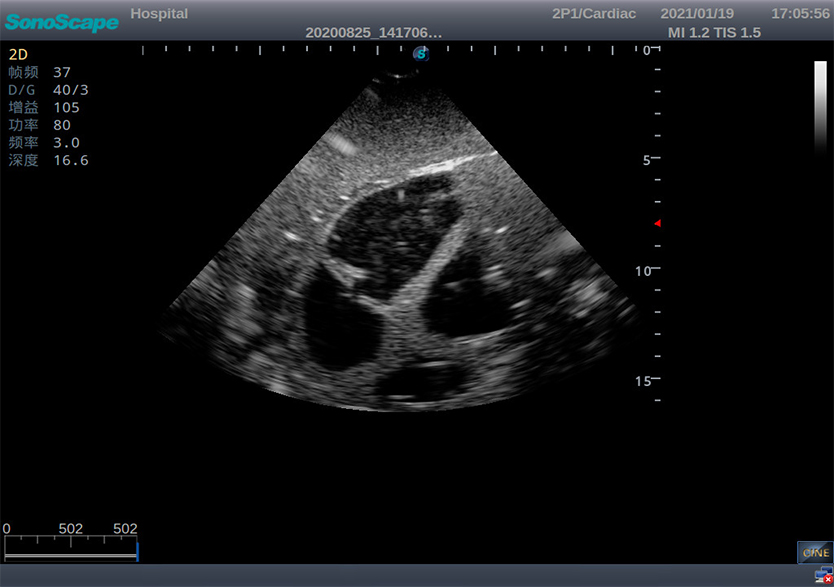

创伤超声重点评估平台2.0

产品型号 NO.TY4084